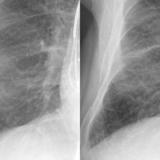

APE 3

Date: 11/05/2005

Views: 3886